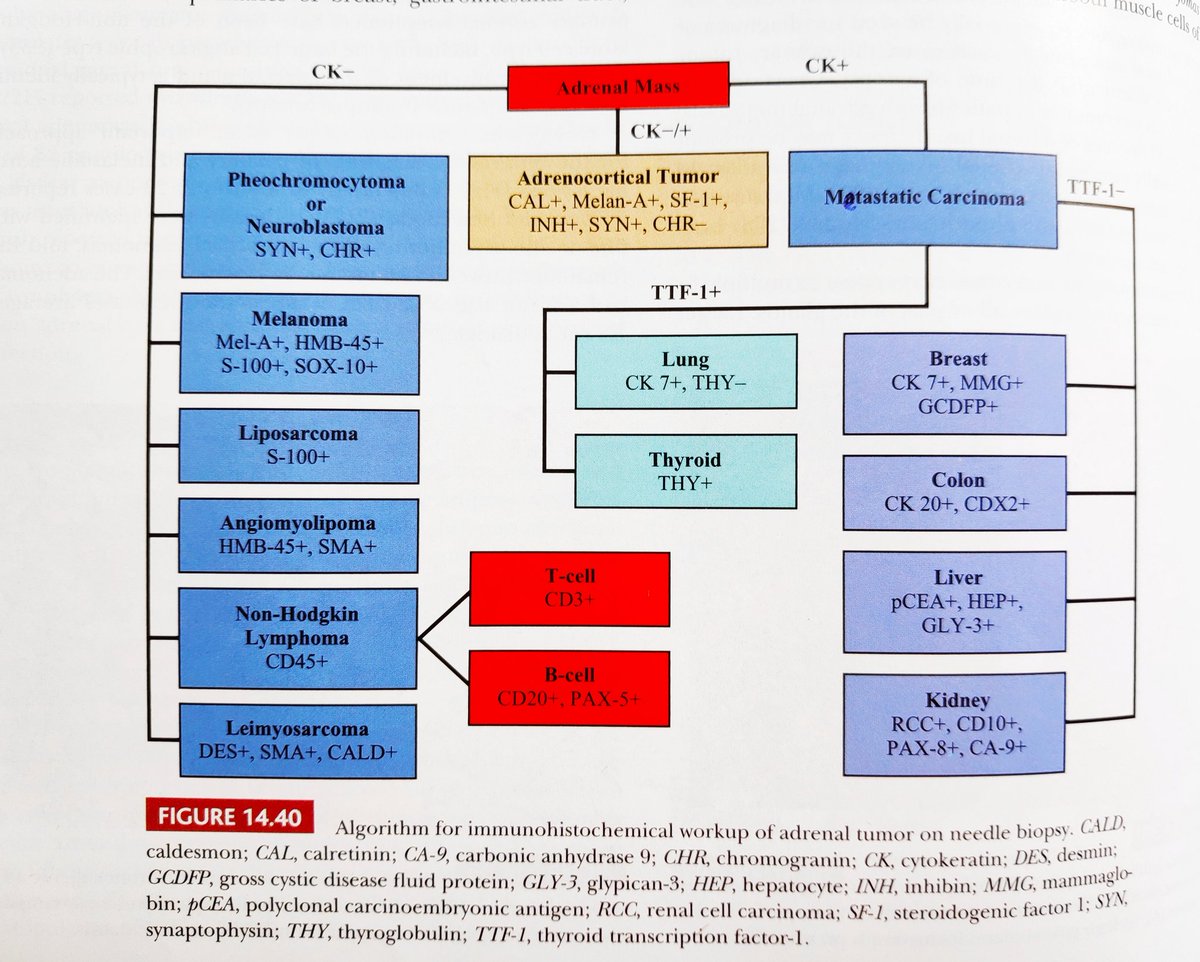

⁉️#GUpath #PEDIpath⚠️ 15YOB with a 7 mm intra testicular nodule... 🔪GROSS🔪 Woo Cheal Cho, MD GU Pathology Society (GUPS) Dr.Gauri Vidolkar MD Frank Ingram, MD Ankur Sangoi @evacomperat Daniel Skipper @AkgulMd Jonathan Zuckerman MD PhD Carla Ellis MD, MS Erasistrate Farshid Siadat, MD, FRCPC Francesca Khani, MD Peter Sadow, MD, PhD Ashish M. Kamat, MD, MBBS Nature Reviews Urology ⏭